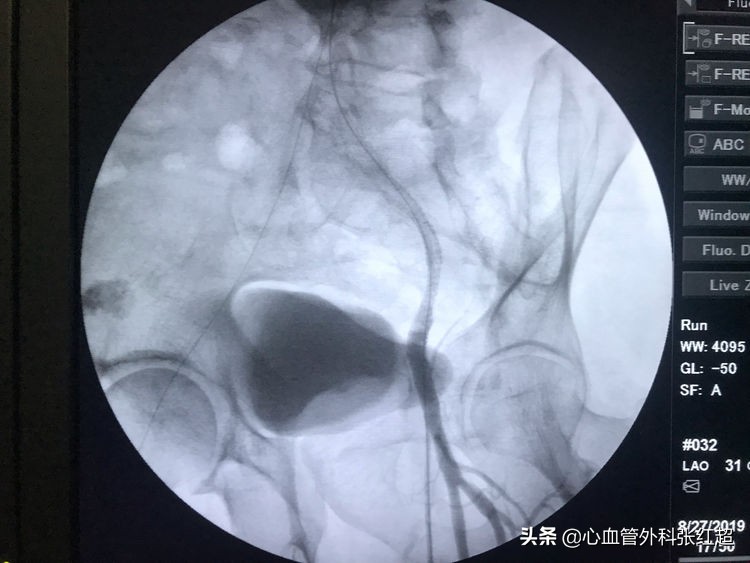

血管造影剂排空快,对侧显影淡,说明血管内血流速度快。

屈曲部稍有残余狭窄。不用硬扩,支架可以在术后贯性序扩。

放两枚支架更容易保证远端释放到位

术后足背、胫后动脉搏动均恢复。